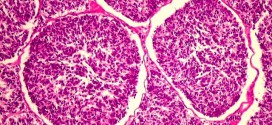

El melanoblastoma. Tumor de células productoras de melanina escasamente diferenciadas. Durante los primeros años de vida de una persona, las células normales se dividen más rápidamente para permitir el crecimiento. El cuerpo está compuesto por billones de células vivas. Las células normales del cuerpo crecen, se dividen formando nuevas células y mueren de manera ordenada. Una vez que se llega …